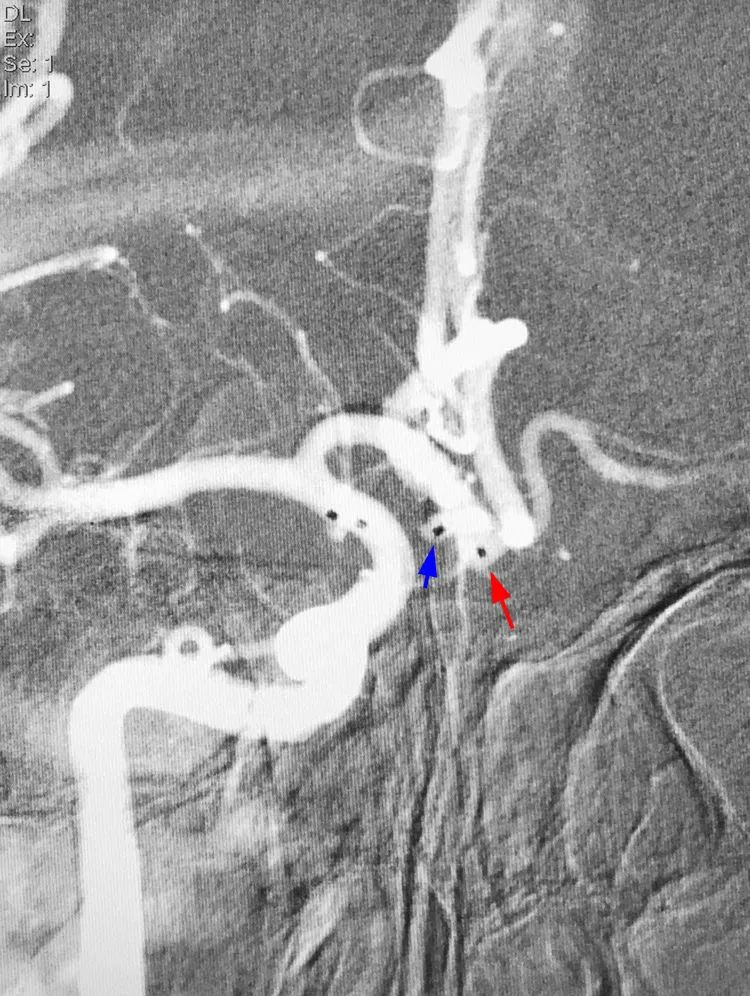

右颈内动脉工作位路图(LAO 3°+CRA 7°)下,第一根Echelon-10微导管(甲管,头端45度预塑形)在Traxcess-14微导丝引导下进入大分叶(红箭);第二根Echelon-10微导管(乙管,头端塑成C形)进入小分叶(蓝箭):